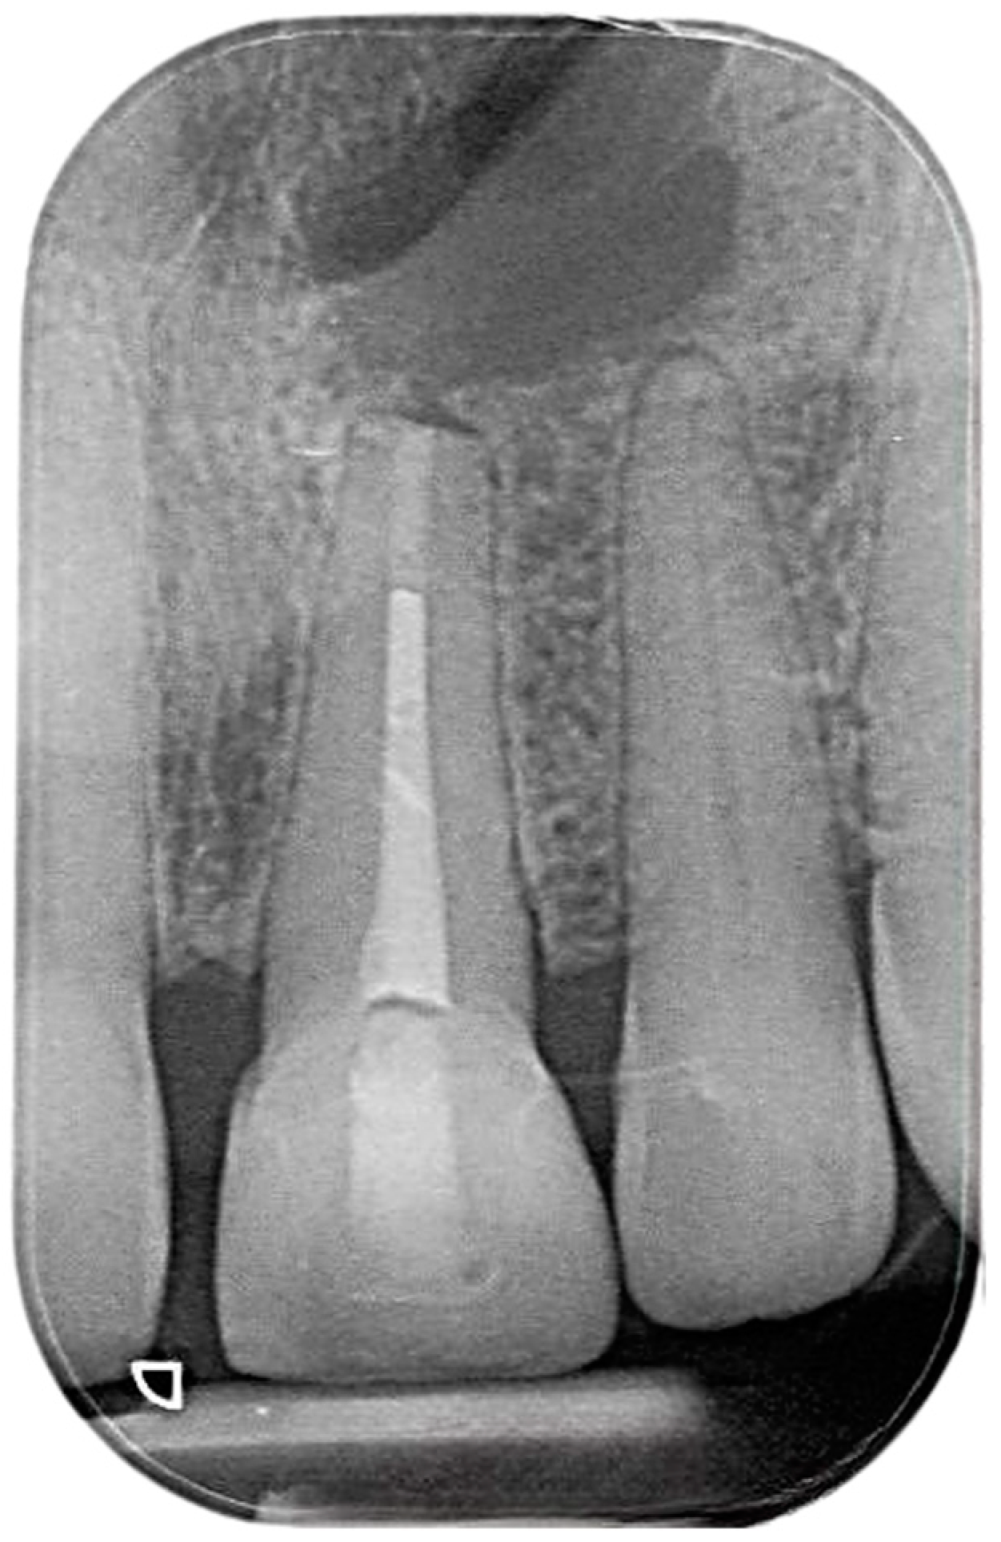

2.4. Healing of the Defect and Follow Up

- Schedule regular follow-up appointments post surgery to monitor the healing process through clinical examination and radiographs.

- Consider annual follow-ups for up to 3 to 4 years to ensure complete healing and adhere to post-apical-surgery guidelines.